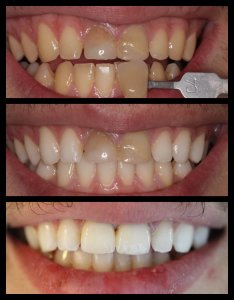

ΛΕΥΚΑΝΣΗ ΔΟΝΤΙΩΝ

ΠΡΟΣΘΕΤΙΚΕΣ ΑΠΟΚΑΤΑΣΤΑΣΕΙΣ ΜΕ ΣΥΝΔΥΑΣΜΟ ΛΕΥΚΑΝΣΗΣ, ΣΥΝΘΕΤΩΝ ΡΗΤΙΝΩΝ ΚΑΙ ΟΛΟΚΕΡΑΜΙΚΩΝ ΟΨΕΩΝ ΚΑΙ ΣΤΕΦΑΝΩΝ